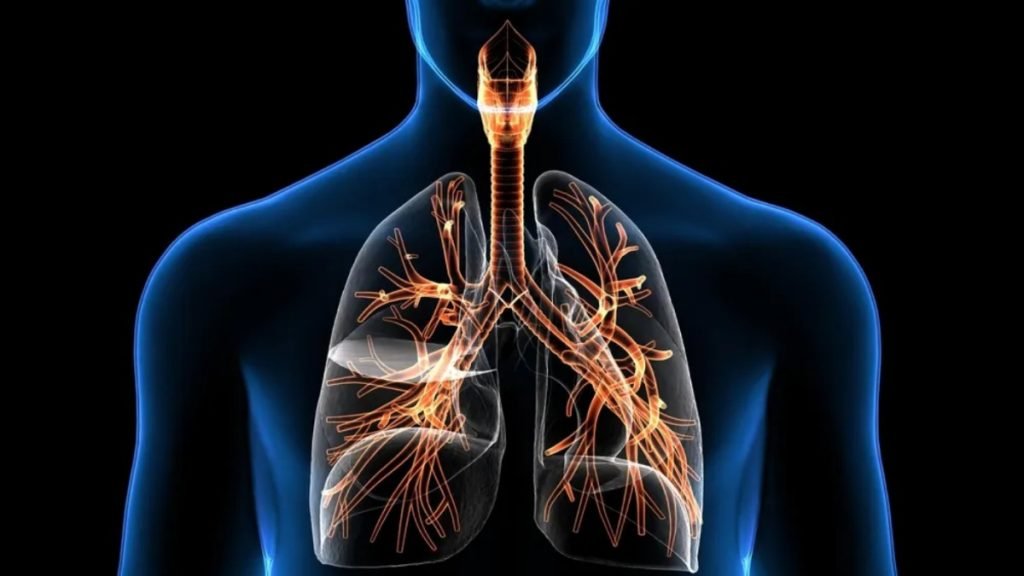

Breathing is life. Every breath we take supplies oxygen to our body and removes toxins in the form of carbon dioxide. However, when this simple act becomes difficult, it signals a respiratory problem. Respiratory diseases have become one of the most common health concerns across all age groups. From mild issues like the common cold […]